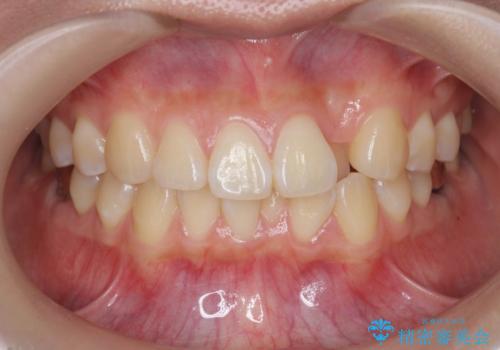

![[ 前歯のねじれ・がたつき ] マウスピース矯正の症例 治療前](https://seimitsushinbi.jp/wp/wp-content/uploads/2024/02/4007c6479f6bce11863dcdd32ed5e39b-500x350.jpg?v=1708502552)